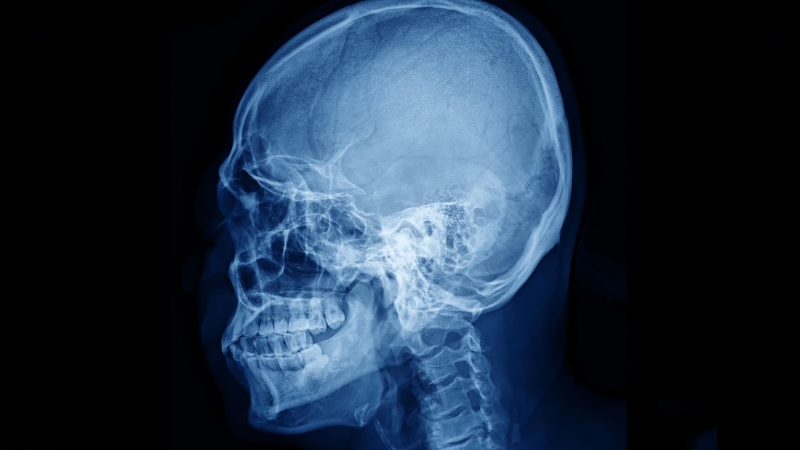

В настоящее время для того, чтобы увидеть сосуды мозга с хорошим качеством, часто приходится истончать кость или делать отверстие в черепе, поскольку костный материал сильно рассеивает лазерный свет и «смазывает» изображение. Именно лазерный свет используется в одном из распространенных методов наблюдения за кровотоком в головном мозге — лазерной спекл-контрастной визуализации, рассказал младший научный сотрудник лаборатории биомедицинской фотоакустики СГУ Юрий Сурков. Из-за рассеяния в кости получаются искаженные карты сосудов и перфузии головного мозга, добавил ученый.

Исследователи СГУ совместно с коллегами из Сеченовского университета, НМИЦ нейрохирургии имени Н. Н. Бурденко, НИУ МИЭТ и Университета Астон (Бирмингем, Великобритания) предложили способ примерно на 100 процентов увеличить контрастность карт сосудов, полученных при наблюдении мозгового кровотока через целый череп. Сосуды стали видны четче, а часть сосудистой сети, которая раньше терялась на фоне кости, проявилась и стала различимой.